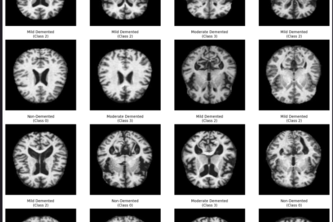

AI-powered Alzheimer's detection from MRI scans. 94% accuracy, 93% early-stage recall. Deep learning tackles 52:1 class imbalance. Clinical-grade performance for timely intervention.